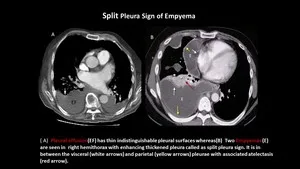

- Imaging (Empyema):

- CECT: Split pleura sign, thickened/enhancing pleura, gas.

⭐ 'Split pleura sign' (CECT): thickened, enhancing visceral & parietal pleura separated by complex fluid; highly suggestive of empyema.